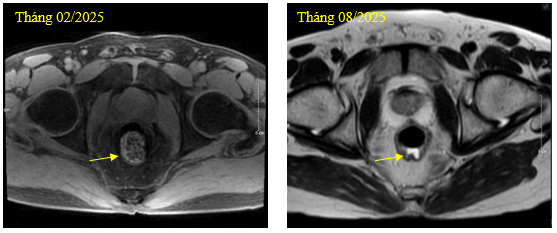

Hình 1. Hình ảnh khối u trực tràng sau điều trị

-        Chụp cộng hưởng từ vùng chậu: Trực tràng giữa dày thành không đều quanh chu vi, dày nhất 10mm, trên đoạn dài ~34mm ngấm thuốc không đồng nhất sau tiêm (giảm kích thước), lân cận có vài hạch, hạch lớn nhất ~13x10mm (không thay đổi).

Hình 3. Hình ảnh u trực tràng trung bình trước và sau điều trị